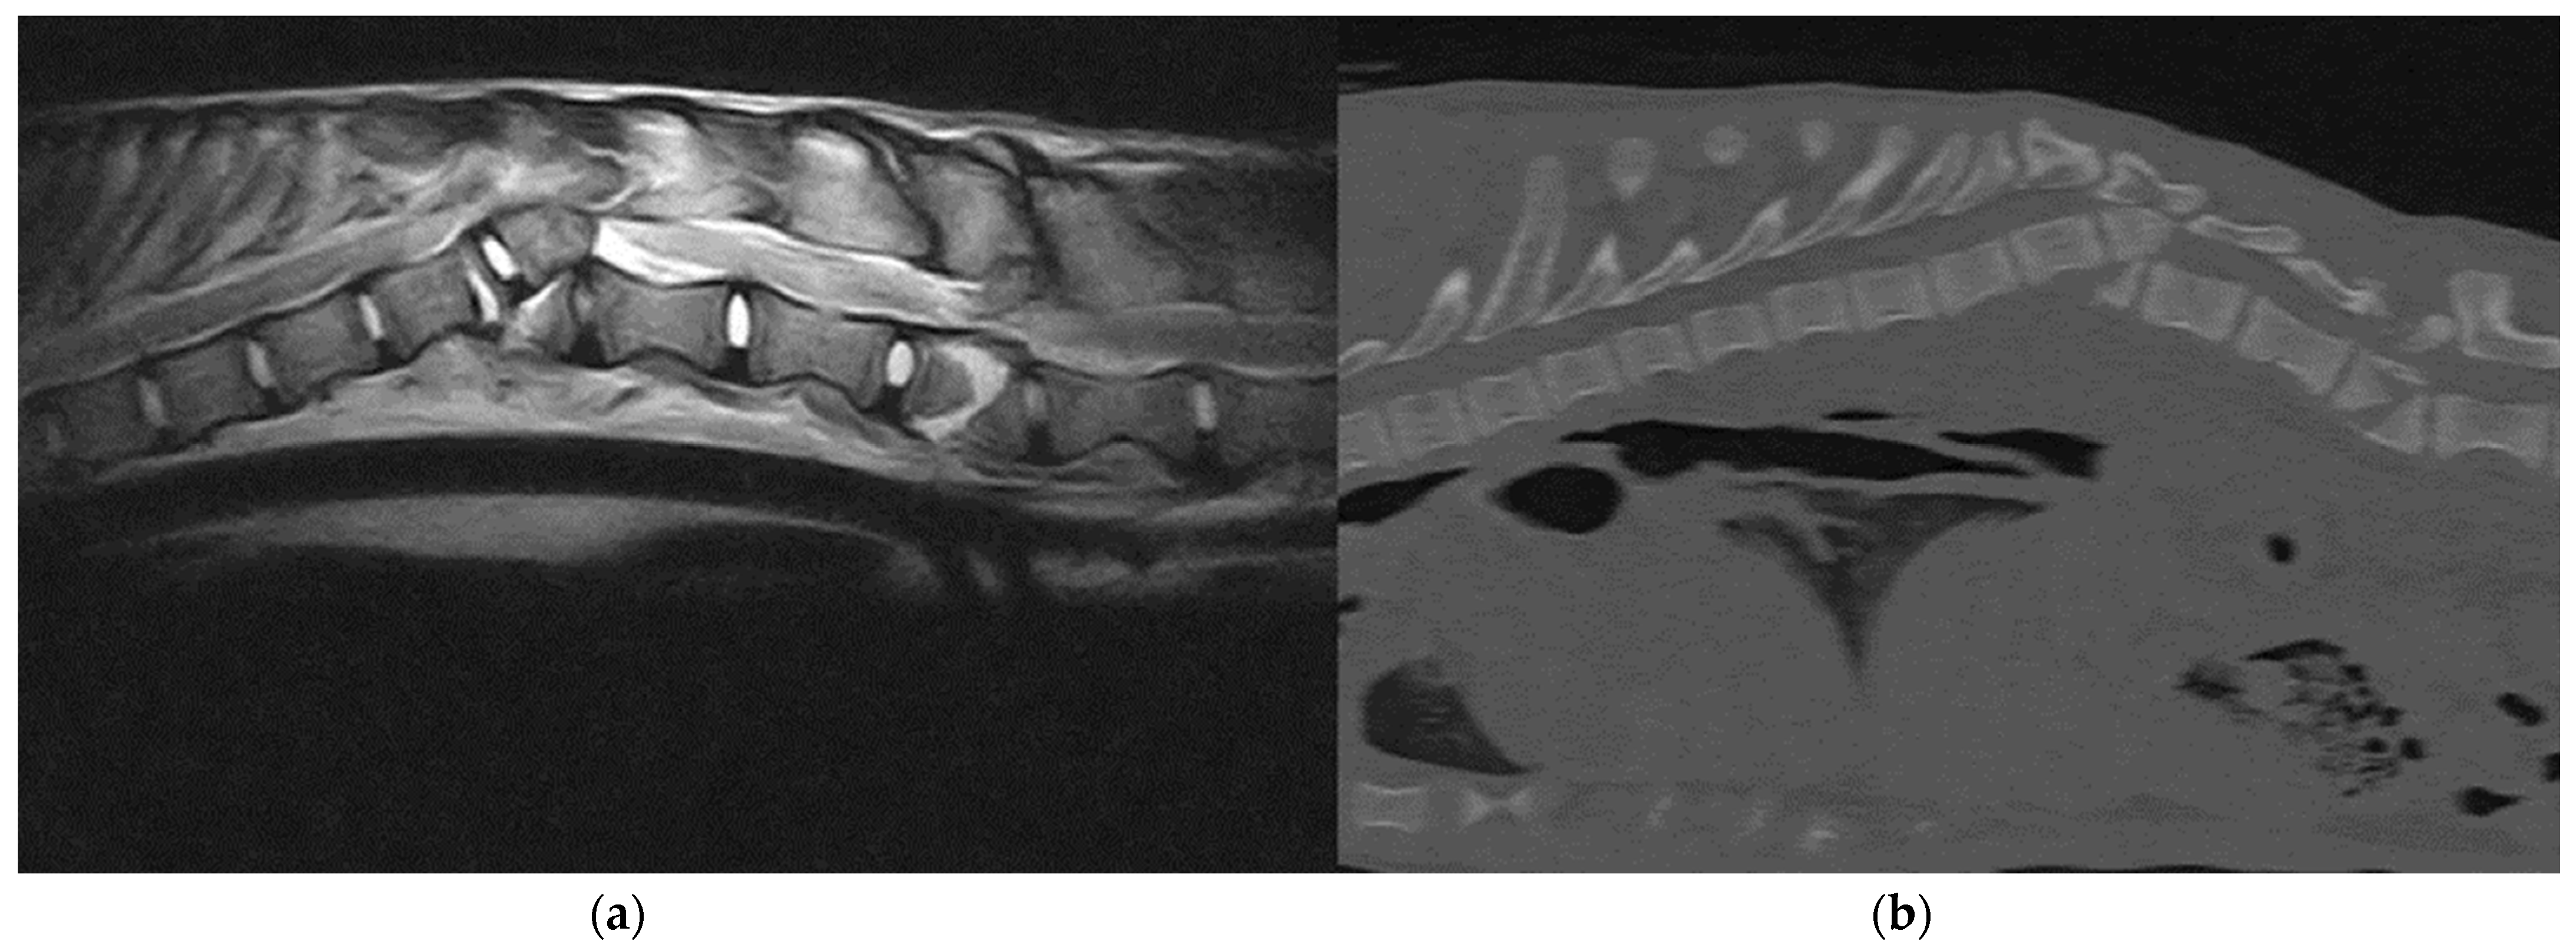

Figure 2.

(a) Sagittal T2-weighted MRI and (b) sagittal bone window CT scan: A 6-month-old, female, Italian wolf affected by vertebral fracture and luxation at the level T12 and L2.

SFLs were confirmed using a digital radiography system and three-dimensional imaging techniques such as MRI and CT. All 14 animals underwent latero-lateral and dorso-ventral radiographic projections of the spine, thorax and abdomen under sedation. Thirteen wolves (92.8%) underwent a total body CT examination, and 11 wolves (78.5%) underwent MRI of the affected spinal segment (Figure 2). Thirteen wolves (92.9%) presented a combination of fractures and luxation/subluxation, and one wolf (7.1%) had only a T12-T13 subluxation secondary to severe discospondylitis, with no fractures. Four wolves (28.6%) presented fractures of two or more vertebrae. Spinal fractures were localized in C1–C5 in one wolf (7.1%), T3–L3 in 11 cases (78.6%) and L4–L7 in two patients (14.3%). Fractures were considered unstable in 12 of 13 fractured wolves (92.3%) because of the involvement of more than one vertebral compartment. At MRI, no wolves showed signs compatible with traumatic disk herniation, six animals (42.9%) presented extended intramedullary hemorrhage and two wolves (14.3%) had a laceration of the spinal cord. Concurrent orthopedic injuries were observed in six patients (42.9%) and involved fracture of the pelvis (n = 3), long bones (n = 2) and ribs (n = 1).